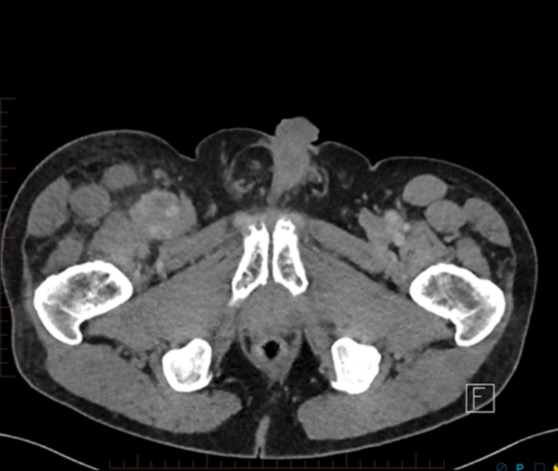

70 male prostate CA with groin mass

FEMORAL ARTERY LEIOMYOSARCOMA WITH BONE METASTASES.

• MORE OFTEN VENOUS THAN ARTERIAL (80%)

• MOST COMMON ARTERY IS PULMONARY ARTERY